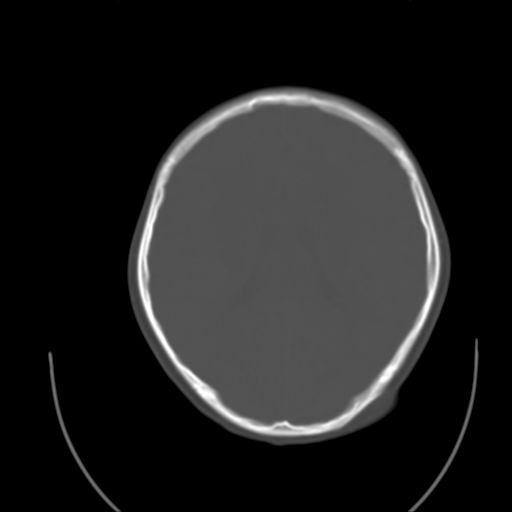

标题: PED1738:男 9岁左枕部包块。 [打印本页]

标题: PED1738:男 9岁左枕部包块。

猛一下想不起这个叫什么了,惭愧,请老师指导~~

左枕部头皮下血肿,有外伤史吗?

枕骨结节

左枕部皮下软组织密度增厚影---考虑-----左枕部头皮下血肿

考虑皮样囊肿可能性大

皮样囊肿可能性大.

皮样囊肿?皮下脂肪瘤?

软组织囊肿性病变可能性大

皮样囊肿?

考虑皮样囊肿。

考虑皮样囊肿可能性大。

皮样囊肿可能性大。